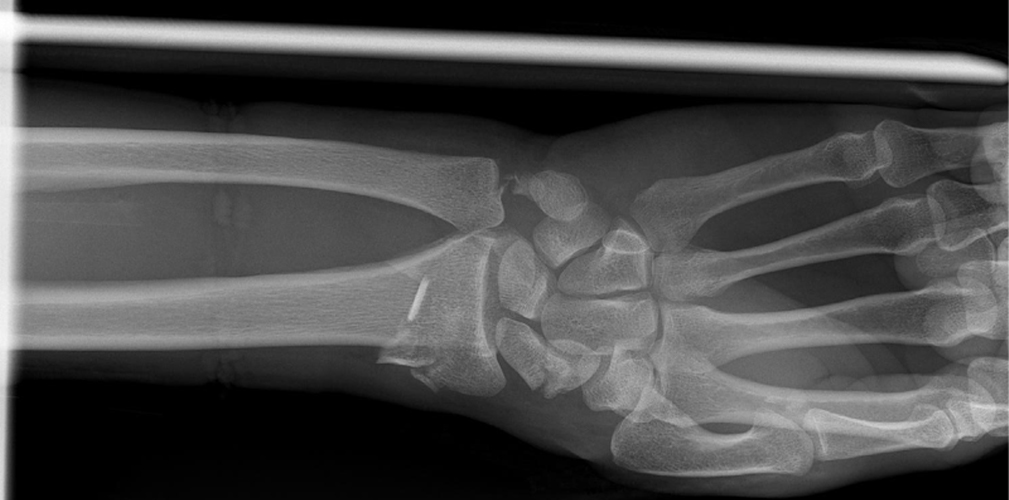

La sera stessa della caduta ho scritto al chirurgo che mi ha operato lo scorso anno (il dottor Pegoli, ndr). Appena ha visto la lastra ha capito che non si trattava solamente di una frattura del radio, ma l’osso era rotto in tre punti diversi. Inoltre, come se non bastasse, si è notata anche una frattura dell’ulna e dello scafoide. Praticamente cinque fratture al posto di una.

La frattura dell’ulna non permetteva di inserire una placca. Quindi i legamenti dovevano rinforzarsi in autonomia e per farlo ci vogliono, in media, sei settimane. Sono tornato in gara al Gran Premio Hindurain e poi al Giro dei Paesi Baschi. Il mio allenatore (Luca Quinti, ndr) è stato bravo a capire come resettare tutto in vista del Giro d’Italia. Dopo le corse in Spagna sono stato due settimane in altura a Sierra Nevada.